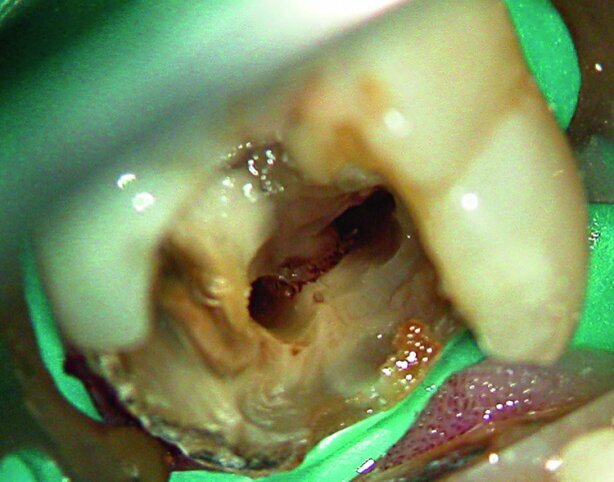

Current techniques are not always completely effective and it has been well recognised that while some part of the root canal are over prepared with rotary instrumentation, other surfaces are not touched. One study concluded that at least 35 % of the surface area of canals had remained untouched by rotary preparation (Peters et al., 2001). In another study the results were even worse, 60–80 % untreated surfaces were left in the distal canals of lower molars, with 65–75 % in the apical 4 mm after preparation (Paque et al., 2010). Oval canals are particularly challenging as the debris collects in the extensions and in isthmuses (Figs. 1a & b).

Fig. 1a: Debris left after root treatment of distal canal of a lower molar.

Fig. 1b: Radiograph of failed root canal treatment shown in Fig.1a.